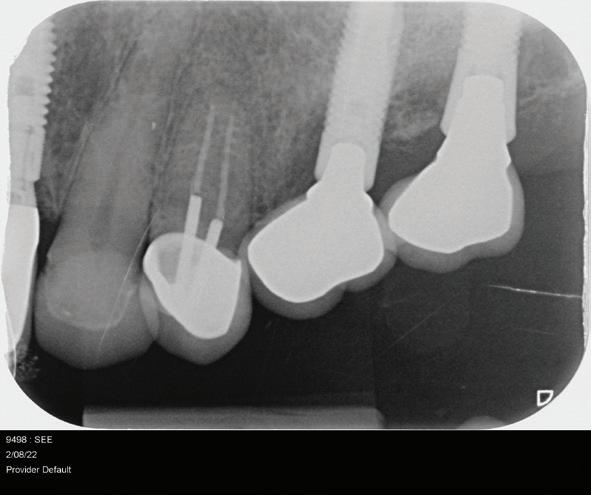

Clear radiographs are essential to accurate diagnosis and are a special test that dentists per form regularly many times throughout the day. Following the ALARA principle, we want to ensure we take a minimal number of radio graphs to ensure low radiation dosage so to repeat radiographs due to operator error should be avoided. The use of film holders allow the clinician to visualise how the radiographs should be taken to optimise the clarity of the image and ensure the diagnostic value of the image. Hawe Solutions x-ray film holders...

Figure 1: Radiographic Image of implants do not demonstrate bone loss due to the bisecting angle of the radiograph taken.

Figure 2: Radiographic image in a paralleling technique of implants dem onstrate moderate peri-implantitis with bone loss that will necessitate treatment.

• Allow exact posi tioning of the film or phosphor plate relative to the tooth - no bending and thus no distortion;

• Require no guesswork - exclusive, automatic reliance on the extraoral aiming and centring device;

• Deliver semi-reproducible images (quasi standardisation)the use of film holders allows some sense of reproducibility for assessment over time; and

• Produce optimally clear radiographs.